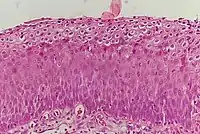

_normal_squamous_epithelium.jpg.webp)

Historically, abnormal changes of cervical epithelial cells were described as mild, moderate, or severe epithelial dysplasia. In 1988 the National Cancer Institute developed "The Bethesda System for Reporting Cervical/Vaginal Cytologic Diagnoses."[12] This system provides a uniform way to describe abnormal epithelial cells and determine specimen quality, thus providing clear guidance for clinical management. These abnormalities were classified as squamous or glandular and then further classified by the stage of dysplasia: atypical cells, mild, moderate, severe, and carcinoma.[13]

CIN is classified in grades:[14]

| Histology Grade | Corresponding Cytology | Description | Image |

|---|---|---|---|

| CIN 1 (Grade I) | Low-grade squamous intraepithelial lesion (LSIL) |

|

![]() |

| CIN 2/3 | High-grade squamous intraepithelial lesion (HSIL) |

| CIN 2 (Grade II) |

![]() | |

| CIN 3 (Grade III) |